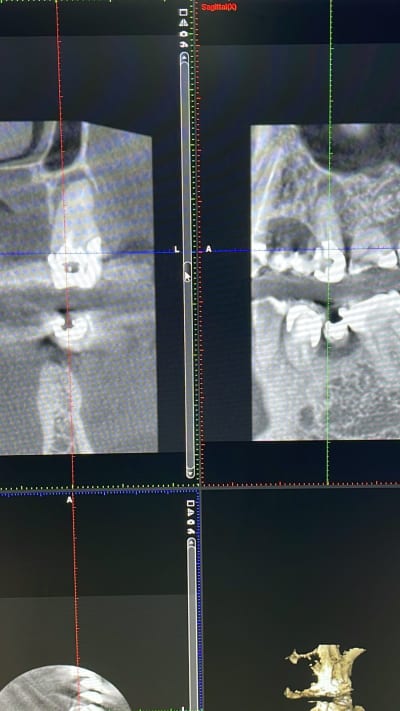

Radio obligatoire pulpotomie

Oui, dentarue, c'est absurde, mais si tu veux gagner du temps pour tes 3D, ecris 01;02 (comme les detartrages) en code de localisation. ca devrait passer :-)

18/04/2023 à 13h38

Ok.

01 c’est le maxillaire et 02 la mandibule ?

On peut entrer ça dans visiodent ou il faut le mettre à la main ?

Je n’ai pas souvenance que le logiciel demande une localisation…

18/04/2023 à 13h39

Mon assistante, quand demandé, écrit le numéro de la dent concernée à la main.

Ni 01 ni 02 et ça passe.

18/04/2023 à 18h24

Tout à fait. La misère.

Je ne vois pas comment faire autrement si visiodent ne demande pas de localisation.

C’est peut-être comme les détartrages mais je n’en ai pas fait un seul depuis 23 ans… Je ne connais rien de la ccam à part les codes endos, je n’ai pas signé pour ça.